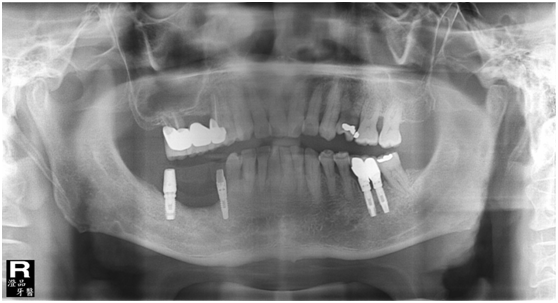

患者之後於96/11/08在右下第一小臼齒與植體間有膿胞產生,並於97/02/21確認右下第一小臼齒有根裂的情形,因此在97/02/29拔除此牙;經過將近半年後,於97/09/23放置一顆植體於此位置

97/02/21 確定根裂時拍的片子

97/02/21

97/09/18 拔牙半年後安排右下第一小臼齒植牙前

97/09/23 右下第一小臼齒植牙完成時

98/01/08經過三個半月做右下第一小臼齒的二階暴露,發覺鄰牙的植體高度竟已掉下來